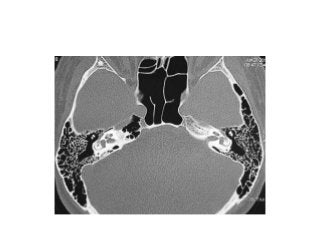

Right ear. Endoscopic anatomy of inferior retrotympanum. fu fustis, t tegmen, pp

posterior pillar, f finiculus, j jacobson’s nerve

Right ear. Endoscopic anatomy of the retrotympanum during

dissection for acustic neuroma surgery.

fu fustis, fn facial nerve, ow oval window, pr promontory, scc

subcochlear canaliculus, et Eustachian tube

Right ear. Endoscopic dissection during surgery, after drilling the

promontory. ow oval window, st scala tympani, scc subcochlear

canaliculus